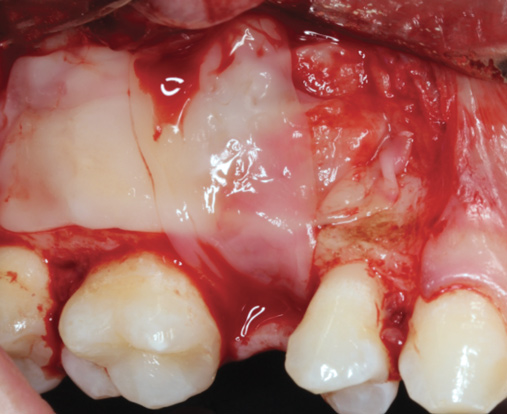

Fig 5. Bone grafting material combined with PRF fragments to fill a medium-sized sinus.

Figure 5

One reported limitation of using PRF alone for sinus augmentation procedures is its use in wide sinuses. Avila et al demonstrated that lateral sinus augmentation procedures performed with an allograft in narrow sinuses (<10 mm) and medium sinuses (10 mm to 15 mm) demonstrated roughly three times more vital bone after a 6-month healing period when compared with wide sinuses (>15 mm) (Figure 4).24 In response to these findings and the clinical experiences of numerous oral surgeons using PRF alone for sinus augmentation procedures, it has been recommended that sinuses >15 mm be regenerated in a combination approach with a bone grafting material. Therefore, all sinuses greater than 15 mm should be regenerated using PRF cut into small fragments with a bone grafting material (Figure 5 and Figure 6).